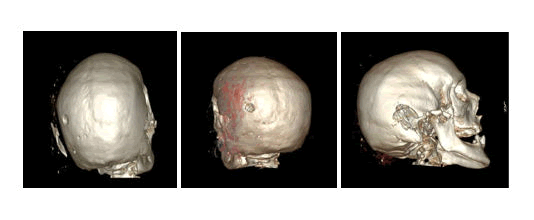

In a specific case that occurred at our facility, a TSRM was assigned the role of a defense consultant following a criminal incident. Based on the criminal charge against the defendant, a defense line was constructed by the defense attorney with the assistance of the forensic pathologist. The pathologist requested the support of a TSRM for the review of post-mortem CT images and the production of new 3D images. Following authorization from the company to undertake extracurricular justice-related assignments, 3D VR images (Figures 3 and 4) and 3D SR images (Figure 5) of the head were reconstructed from CT images produced elsewhere. Images were reconstructed for both bone tissue visualization and skin in various projections and sections to highlight the lesions of interest. Measurements of lesion dimensions and Hounsfield Units (HU) were then made on these images.

The generated result was subsequently compared to the defense thesis. Finally, the produced images served to delineate the degrees of responsibility of the defendants by differentiating non-lethal traumas from those potentially causing death [10].

XXXXXXXX

Figure 3. (Left) 3D VR reconstruction of the cranial vault. (Center) 3D VR reconstruction of the cranial vault from another perspective. (Right) 3D VR reconstruction of the cranial vault with a lateral view.

Figure 4. (Left) 3D slicer VR reconstruction of the cranial vault with a bottom view. (Center) 3D slicer VR reconstruction of the cranial vault from another perspective. (Right) 3D slicer VR reconstruction of the cranial vault with a lateral view.